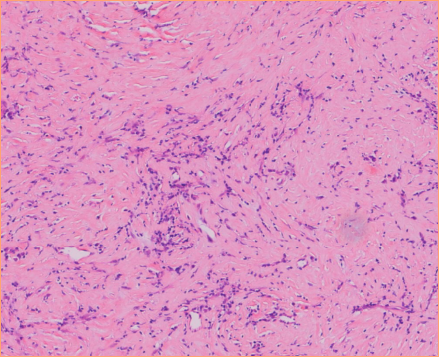

High Image Quality for Digital Pathology

KFBIO Digital Pathology Slide Scanner (PRO) is a world leader in the accuracy of movement, focus, and image processing, and its accurate whole slide imaging not only meets the requirements of digital slide viewing and operation but is also suitable for AI-assisted image analysis.

High Quality, 3 Colors Independent Processing

K-SCP color processing method helps restore the original color, saturation, color temperature, color contrast and other indicators to enhance images, as well as color compensation of different displays after imaging.

High Resolution, 0.5µm/pixel (20X), 0.25µm/pixel (40X)

It adopts top optical accessories. The light source, objective lens, camera, optical path and other accessories are comprehensively optimized. It greatly improves the optical resolution to directly observe the structure and details in the cell. The nucleus edge is sharp and the internal structure is clearly visible. The resolution distance can be as small as 0.125µm.

High Precision, 20nm Fine Control, 80x magnification

Linear magnetic axis drive and grating ruler positioning mechanism are adopted to achieve ultra-high precision of image movement control and image positioning at the nanometer level. It helps sample fast and accurately to achieve stable imaging for a longer period of time. The magnification can reach 80x.